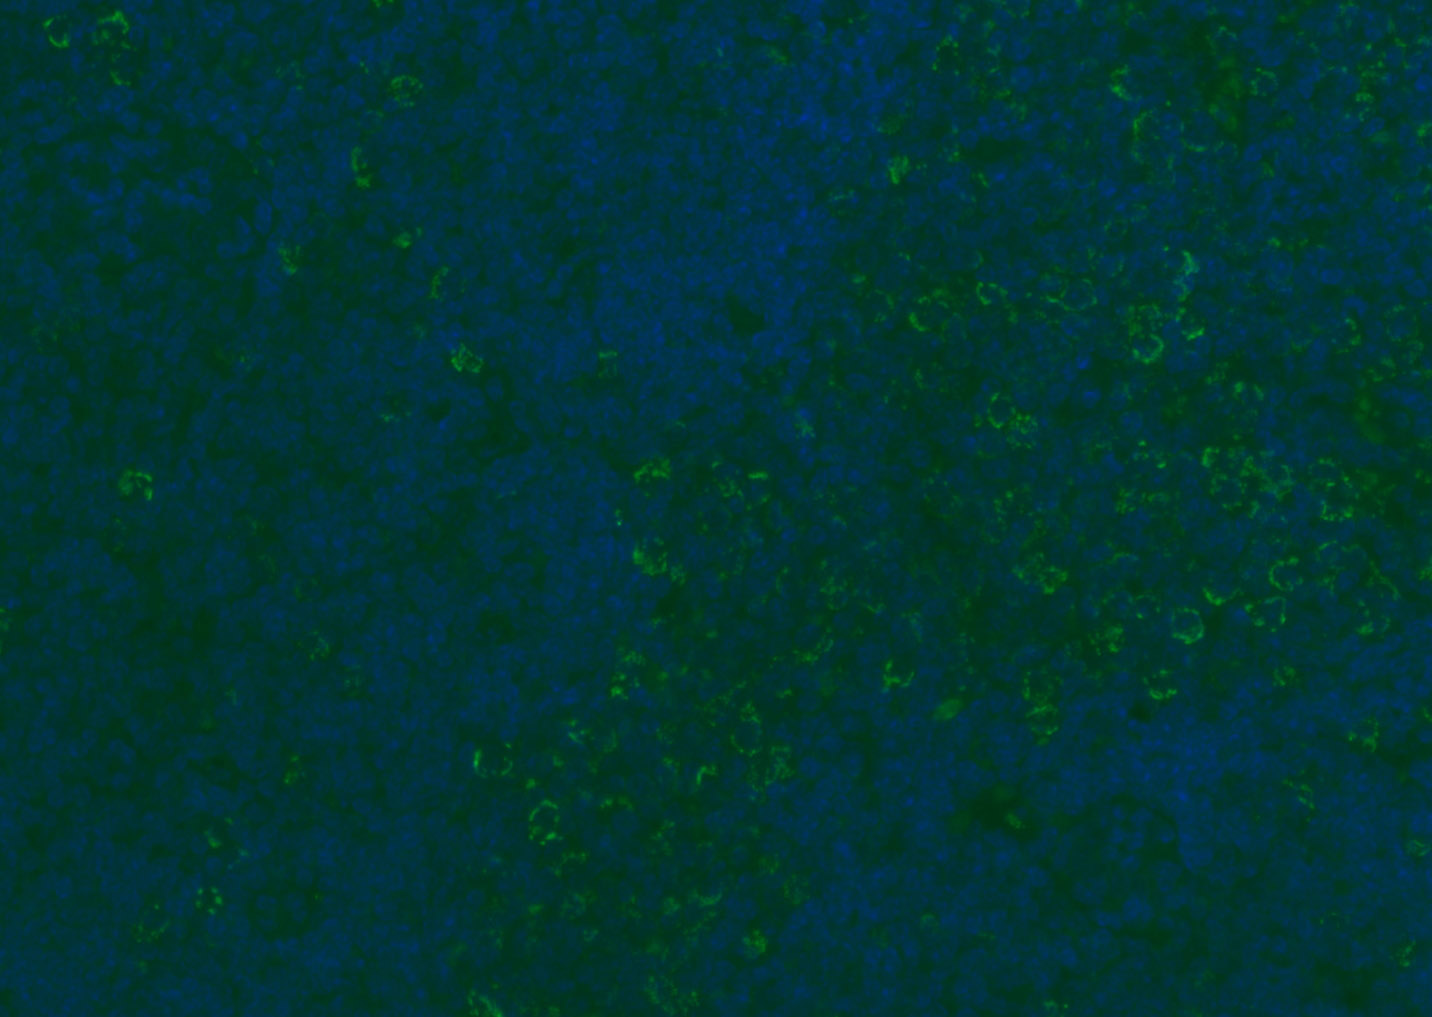

Tissue/cell: human lung carcinoma;4% Paraformaldehyde-fixed and paraffin-embedded;

Antigen retrieval: citrate buffer ( 0.01M, pH 6.0 ), Boiling bathing for 15min; Blocking buffer (normal goat serum,C-0005) at 37℃ for 20 min;

Incubation: Anti-CD8 Polyclonal Antibody, Unconjugated(bs-4914R) 1:200, overnight at 4°C; The secondary antibody was Goat Anti-Rabbit IgG, Cy3 conjugated(bs-0295G-Cy3)used at 1:200 dilution for 40 minutes at 37°C. DAPI(5ug/ml,blue,C-0033) was used to stain the cell nuclei